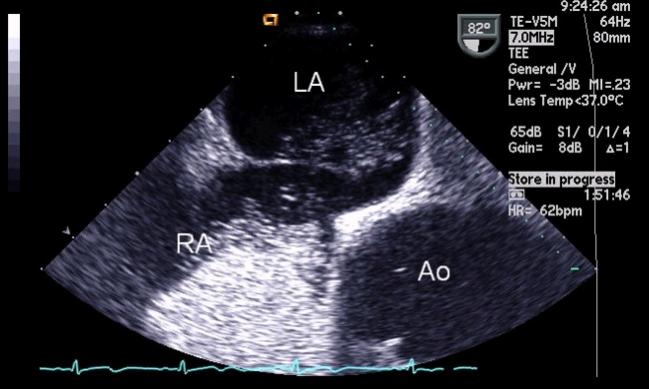

An Echo Bubble Study is an injection of saline after agitation with air to create micro-bubbles that are ultrasound reflective into a vein in order to reach and opacify the right heart chambers the coronary sinus in cases of persistent left superior vena cava PLSVC or the pericardium during pericardiocentesis. Bubble studies are used to identify if a patient has a PFO patent foramen ovale--in which there is communication between the right and left atrium. A bubble echocardiogram is typically performed by an ultrasound technician.

Comparing TEE as the gold standard TCD detection of PFO has a sensitivity of 95 and specificity of 75. A bubble study is a type of echocardiogram which is the ultrasound of the heart. After obtaining optimal visualization of atrial septum on TTE or TEE a bolus of agitated saline is injected to an antecubital.

I assist with TEEs all the time in my dept. Bubble Study during TEE Medical Billing and Coding Forum - AAPC. While transesophageal echo TEE bubble study is the current standard reference for diagnosing PFO transthoracic echo TTE remains the most commonly used screening test for RLS due to its noninvasiveness and easy availability.

For the bubble study you will get an intravenous IV line in a vein in your arm. If the contrast study is positive for a RLS a TEE is required to define the anatomy of the atrial septum assess its suitability for device closure and ideally to confirm that the shunt is due to a PFO rather than a pulmonary shunt or other defects of the atrial septum. An echocardiogram is done to visualize the heart and its surrounding areas.